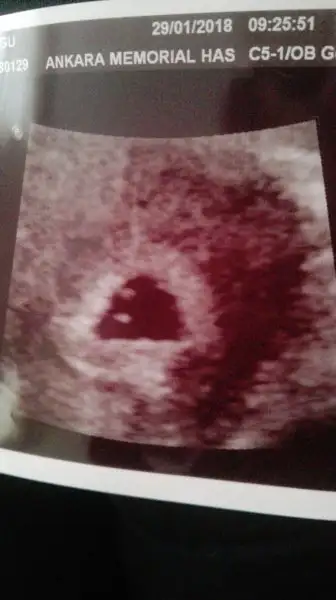

merhaba kızlar.bende eylül de anne olacağım inşallah. 5 hafta 5 günlükken ultrasonda göründü kese ama ilginç ki 2 kese var. ve dr bana ikiz yada başka birşey demedi. hayırlı olsun çok sağlıklı dedi. kalp ritmi görünüyor ama tüm tahliller için 1 hafta sonra yeniden bakalim dedi. ultrason goruntume bi bakar mısınız sizde lütfen

bana bir kese kese içinde 2 noktacik var gibi geldi bi yanlışınız var

Brn tek kese gördüm doktorun da ikiz olsaydı söylerdi. Kesen aynı kızımın kesesi gibi üçgen :) çok sağlıklı ve güzel geçmişti benim kızumdaki serüvenim, inşallah senin de öyle geçer.